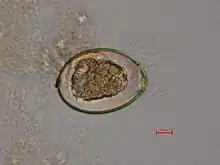

D. latum tiene un escólex alargado y, a diferencia de otros cestodos, tiene discos succionadores en lugar de ventosas. Los huevos son ovales y tienen un opérculo en forma de tapa.

Demostración de huevos con opérculo en las evacuaciones o proglótides que son más anchas que alargadas (con patrón en roseta de las ramas uterinas) en heces o vómito.